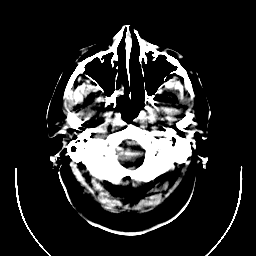

CT Study #1 -- Slice #1

[Home][Help][Clinical][Tour 1] Slice 1